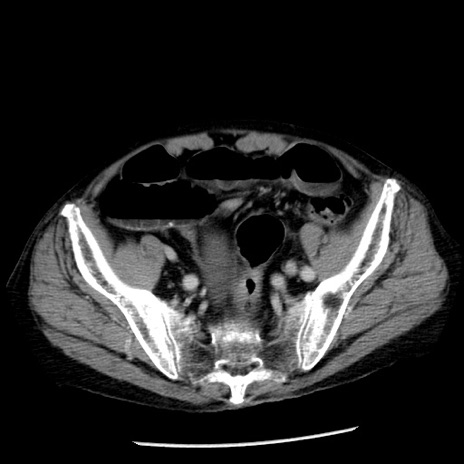

症例26(横断像)

【症例】80歳代男性

【主訴】嘔吐

【現病歴】昨晩2回嘔吐あり、今朝になっても嘔吐あり。来院。

【既往歴】胃潰瘍

【身体所見】意識清明、BT 37.6℃、BP 166/95mmHg、HR 100bpm、SpO2 97%、腹部:平坦・軟、腸蠕動音聴取良好、圧痛なし。

【データ】WBC 21900、CRP 1.46